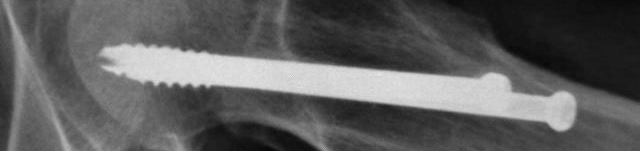

股骨颈骨折采取钢钉固定,若已达到愈合标准可以取出钢钉。这需要住院手术,毕竟需要麻醉,一般三五天,最快两三天即可出院。

如决定入院取出钢钉,需要做好相应的术前准备,包括抽血化验:血常规、尿常规、肝功肾功、血糖、电解质、肝炎系列、艾滋梅毒、凝血功能等,这些在早晨6点钟空腹采血;检查:患部X线、胸部X线、心电图。